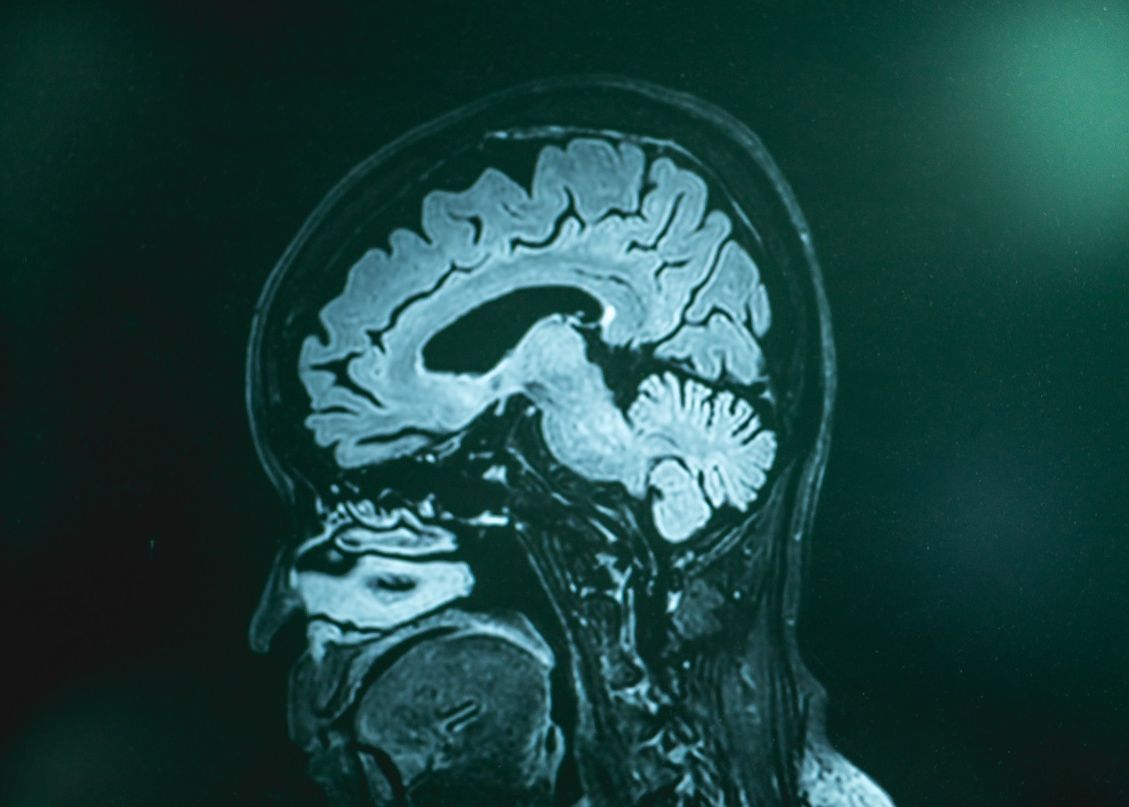

Într-unul dintre studii, reducerea nivelurilor NO2 a scăzut, în timp, riscul de a dezvolta demență cu până la 26%. Atunci când sunt inhalate, particulele microscopice poluante intră în circuitul sanguin și ajung la creier, acolo unde provoacă inflamarea celulelor - o problemă care poate fi una dintre cauzele demenței. Totuși, este nevoie de mai multe cercetări pentru a afla exact care este corelația dintre cele două.

PM2.5 poate pătrunde cu ușurință în plămâni și apoi în fluxul sanguin și provine mai ales din arderea cărbunilor, lemnului, incendii de pădure, dar și alte tipuri de procese derulate de oameni. La rândul său, NO2 - găsit mai ales în emisiile autovehiculelor - distruge celulele sistemului imunitar și crește riscul de dezvoltare a infecțiilor respiratorii.